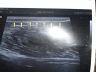

Jeferson foi até a instituição de saúde e procurou dialogar com o médico que o atendeu. “Mas ele não queria aceitar que tinha uma agulha na minha veia. Disse que seria sangue coagulado. Mas depois de muita insistência ele voltou atrás e fez um ultrassom e confirmou que havia um objeto estranho na minha veia. Isso era umas 13h e fiquei em uma sala esperando. Às 17h aconteceu a cirurgia. Só que o médico não queria deixar eu ver a cirurgia. Chegou a falar que não tinha nada. Se não tivesse nada, um ponto seria o suficiente. Mas deram cinco pontos após tirar a agulha. Vi o médico puxar algo de minha veia”, garantiu Jeferson.

Após passar por momentos de tensão, Jeferson afirmou à reportagem estar indignado. “Passei uma semana com uma agulha em minha veia. Tenho como comprovar através de imagens e de conversas gravadas”, afirmou.